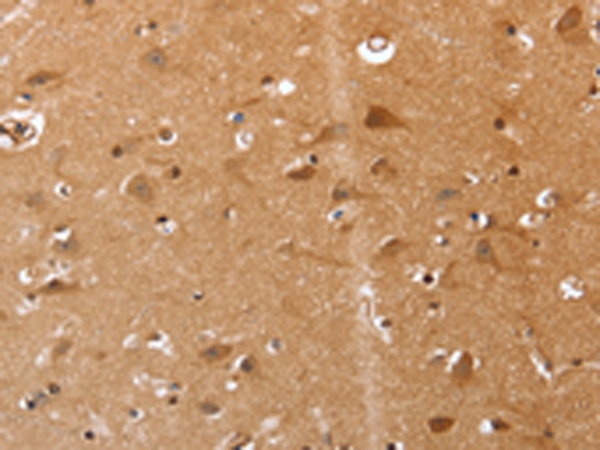

IHC positive control: |

Human brain and Human renal cancer |

IHC Recommend dilution: |

25-100 |